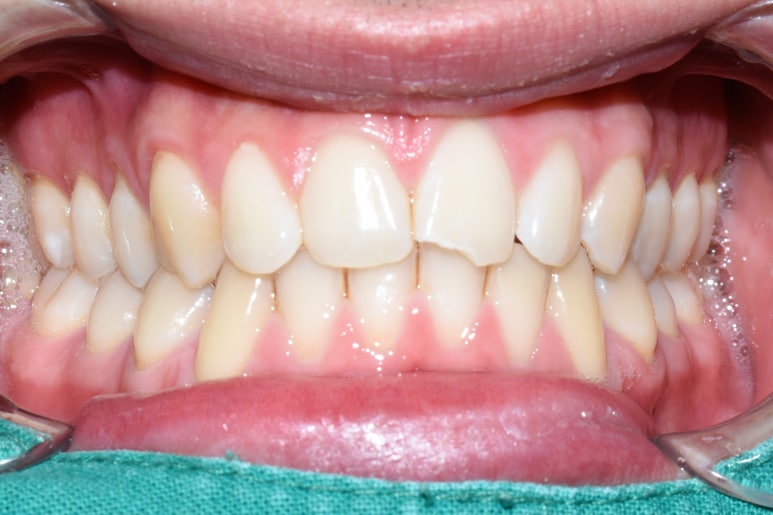

파절 앞니 레진 전후

앞니 벌어진 부위는 부분교정, 무삭제 부분라미네이트, 무삭제 라미네이트, 레진 등

그 공간을 메우는 여러 방법이 있지만

케이스에 맞는 방법을 고르는 것이 중요하므로 원장님과 상담이 필요합니다!

저희 시청역 연세예감치과는 다양한 shade의 레진을 구비하여

앞니레진을 하였을 때 최대한 티가 나지 않게,

또는 자연스럽게 더 밝아지면서도 티가 나지 않게 노력하고 있습니다.